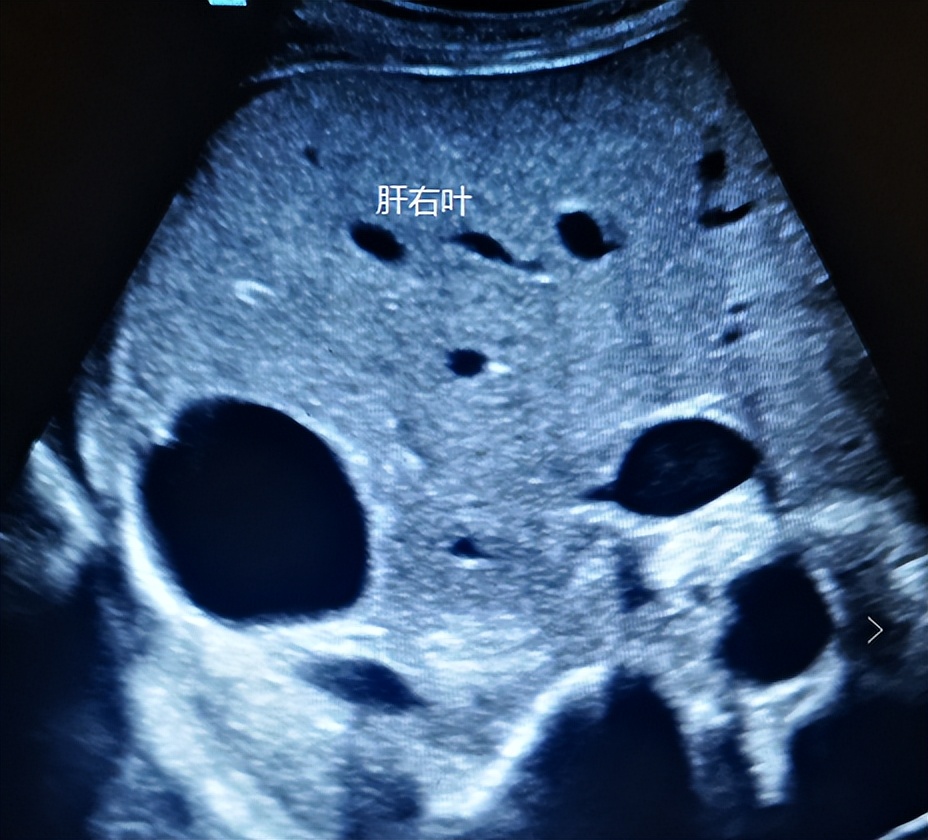

如下图,看似肝囊肿。

换个切面扫查,实则肾囊肿。